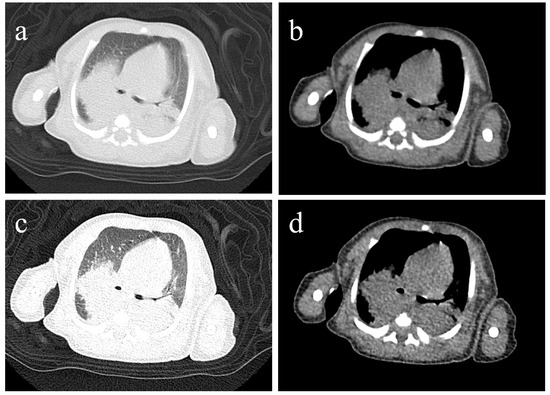

Severe Pertussis During Early Infancy from a High-Altitude Region: Two Clinical Cases and Literature Review

Objective: To investigate how the high-altitude environment modifies severe pertussis in young infants and analyze its pathophysiological mechanisms and clinical management implications. Methods: Clinical data of two young infants with severe pertussis residing at 3650 m were retrospectively analyzed, including presentation, laboratory findings, pathogen detection, treatment, and outcomes. A literature review explored synergistic interactions between high-altitude factors and pertussis pathophysiology. Results: Case 1 had macrolide-resistant Bordetella pertussis (MRBP, 23S rRNA A2047G) with peak WBC 52.25 × 109/L, and received cefoperazone-sulbactam, piperacillin-tazobactam and azithromycin, and was successfully treated with trimethoprim-sulfamethoxazole combined with exchange transfusion. Case 2 had Bordetella pertussis confirmed by PCR with peak WBC 36.55 × 109/L, receiving cefoperazone-sulbactam and azithromycin, and recovered. Both developed respiratory failure requiring non-invasive ventilation and survived without pulmonary hypertension. High-altitude stressors—hypoxia, enhanced pulmonary vascular reactivity, and hypercoagulability—synergize with pertussis-induced hyperleukocytosis as a “dual hit,” accelerating cardiopulmonary deterioration and elevating thrombotic risks. Conclusions: High altitude is an independent risk modifier in infantile pertussis, demanding heightened vigilance and proactive interventions: early non-invasive ventilation, prophylactic anticoagulation, and timely exchange transfusion before pulmonary hypertension develops. This is the first high-altitude case series that provides essential insights for clinicians in similar environments globally, guiding early recognition and proactive management strategies to improve outcomes in this vulnerable population. Full article

Figure 1